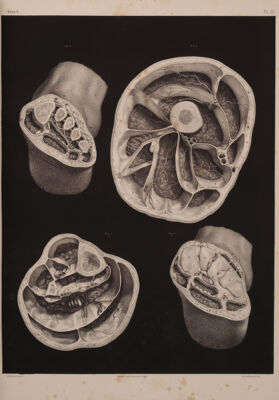

Traité complet de l'anatomie de l'homme comprenant la médecine opératoire ... : avec planches lithographiées ... / par N.H. Jacob.

- Jean-Baptiste Marc Bourgery

- [1831-1854]

Credit: Traité complet de l'anatomie de l'homme comprenant la médecine opératoire ... : avec planches lithographiées ... / par N.H. Jacob. Source: Wellcome Collection.